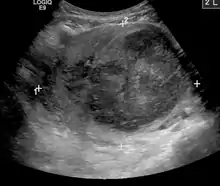

- Kidney cancer: kidney tumors such as renal cell carcinoma can be treated with image guided ablation (RFA, MWA, cryotherapy) with similar results to partial nephrectomy. Generally, surgery via an either partial or total nephrectomy (removal of kidney) is most often curative but for patients with a smaller lesion or who are not ideal surgical candidates, radiofrequency or cryoablation ablation can be a curative option.[70] Advantages of cryoablation include the ability to visualize the ice ball as well as use more than one probe simultaneously to create the desired ice ball shape. Benign kidney tumors such as angiomyolipomas can be treated with transarterial embolization to shrink the tumor size and reduce the risk of rupture/bleeding. Other embolizations are also performed for symptom relief or prior to surgery to reduce bleeding[71]